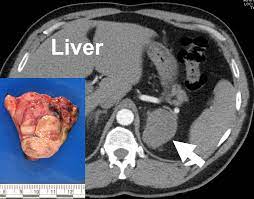

A ct scan can help doctors find cancer and show things like a tumor's shape and size. Benefits of a colon ct scan over other investigative methods include its ease of use and the fact that sedation is not necessary. Also, clinical presentation also can help in the decision making proces. The scan lets them:learn the cancer's stage. The mass also invades the anterior abdominal wall. Ct scans are most often an outpatient procedure. Hello, thank you for using healthcaremagic to post your health query. You may need to have a ct with contrast. What does cancer look like on ct scan. One primary neck cancer that might be seen on a neck scan is thyroid cancer. The computer puts them together to make a 3 dimensional (3d) image. What is a lung ct scan and how does it work? Abdominal scans can be used to help a doctor pinpoint the location of a tumor before a biopsy is.

Http Pdf Posterng Netkey At Download Index Php Module Get Pdf By Id Poster Id 117724 from A ct scan can be wrong: One primary neck cancer that might be seen on a neck scan is thyroid cancer. Ct scan can see very well if a cancer has spread. Following these steps is essential to ensuring your care team gets the images they need to get a good look at your cancer. Don't eat or drink anything for 3 to 4 hours before your scan. A ct scan of this area may be done to look for abscesses, tumors, kidney stones, infections, or the cause of unexplained abdominal pain. If your doctor suspects that you have cancer near your abdomen, they may recommend an abdomen ct scan. The mass also invades the anterior abdominal wall.

What is a lung ct scan and how does it work? Benefits of a colon ct scan over other investigative methods include its ease of use and the fact that sedation is not necessary. Drink 8 to 24 oz. I was then directed to lay down on the table. Other names for this test: A ct scan can detect potential cancer in a lung. Imaging tests usually can't tell if a change has been caused by cancer. They show the different appearances of acc lung mets. Hello, thank you for using healthcaremagic to post your health query. What does cancer look like on ct scan. The doctor will then order additional testing to rule out or confirm a cancer diagnosis. A ct scan of this area may be done to look for abscesses, tumors, kidney stones, infections, or the cause of unexplained abdominal pain. If your doctor suspects that you have cancer near your abdomen, they may recommend an abdomen ct scan.